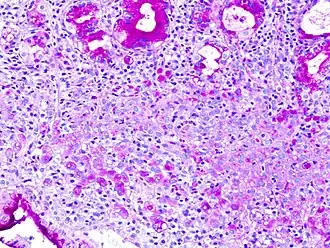

Signet ring cell, as seen in a case of colon adenocarcinoma with mucinous features, showing a tumor cell with a vacuole of mucin. H&E stain.

In histology, a signet ring cell is a cell with a large vacuole. The malignant type is seen predominantly in carcinomas. Signet ring cells are most frequently associated with stomach cancer,[1] but can arise from any number of tissues including the prostate,[2] bladder, gallbladder,[3] breast, colon,[4] ovarian stroma and testis.[5]

The name of the cell comes from its appearance; signet ring cells resemble signet rings. They contain a large amount of mucin, which pushes the nucleus to the cell periphery. The pool of mucin in a signet ring cell mimics the appearance of a finger hole and the nucleus mimics the appearance of the face of the ring in profile.

SRC carcinomas can be classified using immunohistochemistry.[8]